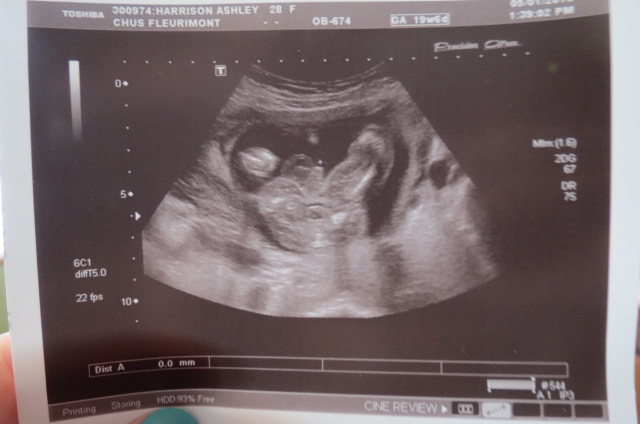

My friend had done an ultrasound at 16 weeks, 2 days and it wasn't very clear... I rewatched my video and caught this!

What do you think?

IT'S A BOY!!!

Attachment 29184